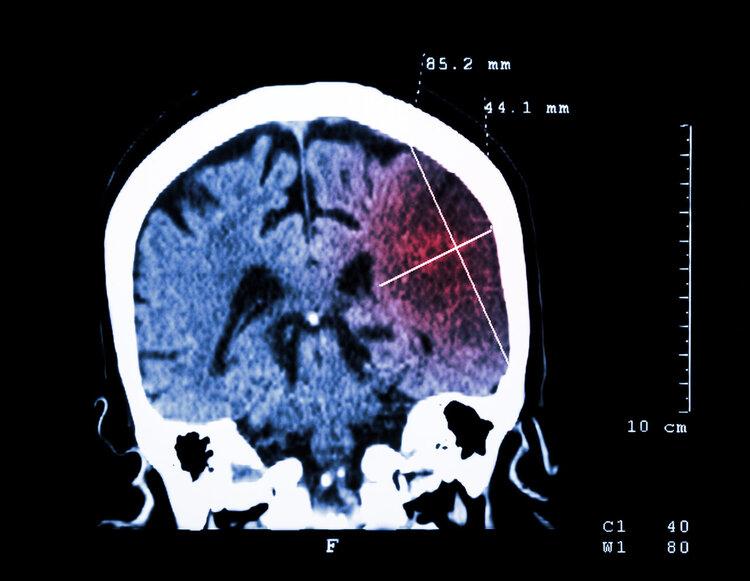

近日,69歲的張大伯突然出現言語不清、肢體無力等症狀,幸好家人及時發現,並撥打了急救電話120,結果送醫被診斷爲急性腦卒中。

經過急診醫生積極的溶栓治療,張大伯成功脫險,而且不適症狀有所緩解,住院不到一週,張大伯就已經恢復得很好,和家人高高興興回家了!

02、65歲女子突發腦梗,家屬喂服安宮牛黃丸,慘遭偏癱

劉阿姨今年65歲,自從退休後便加入公園裏的廣場舞大軍,每天都要跳跳舞。一天晚飯後正收拾完想要去跳舞,結果突然頭暈不已、手腳無力、癱倒在地。

家人和她對話發現她言語不清,擔心是中風,便想起家中備有安宮牛黃丸,就讓她喫了。但家人發現她服藥後症狀不但沒有好轉,反而嚴重了,這時候才撥打了120急救電話。

雖然劉阿姨經過積極搶救撿回了性命,但卻錯過了最佳溶栓時間,最終落下了偏癱的後遺症